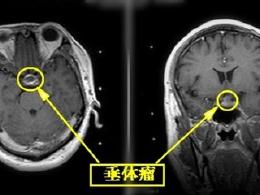

看不清东西未必是眼的错,可能是垂体瘤在作祟!当视物不清时,相信大多数人都会先去看眼科查找原因。其实,看不清东西未必都是眼睛的错。有一种长在脑袋里的良性瘤,也会导致同样的症状,却常常被误诊。今天就来跟大家介绍这种隐蔽性较强的垂体瘤到底还有什么症状,对身体的影响及其治疗手段。 垂体瘤是一种良性腺瘤 垂体瘤是...

\ _ / 看不清东西,未必是眼睛的错!可能是垂体瘤!当视物不清时,相信大多数人都会先去看眼科查找原因。其实,看不清东西未必都是眼睛的错。有一种长在脑袋里的良性瘤,也会导致同样的症状,却常常被误诊。今天就来跟大家介绍这种隐蔽性较强的垂体瘤到底还有什么症状,对身体的影响及其治疗手段。 01 垂体瘤是一种良性腺瘤 垂体...